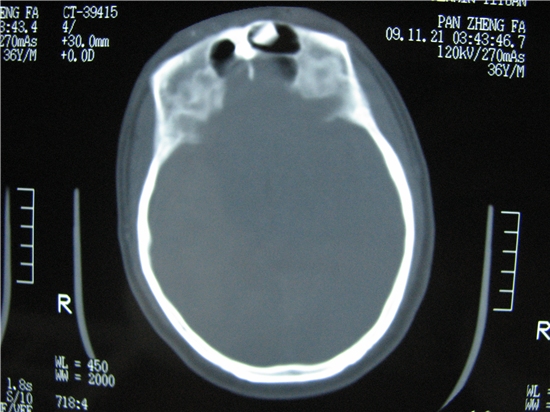

标题: CT23231:男 32岁 车祸伤,鼻腔内出血明显。 [打印本页]

标题: CT23231:男 32岁 车祸伤,鼻腔内出血明显。

额窦里是什么,骨窗怎么不清晰,是不窗宽窗位的事。

软组织及额窦内异物

不排除鼻骨骨折!额窦骨瘤?

额窦内及额部软组织内可见多发游离类骨质密度影,考虑额骨骨折可能。

额窦内应该是正常的,和体位有关系,当你用三位重建就知道了

额窦致密骨瘤,前额部及右顶部头皮损伤伴异物存留

左侧额骨、鼻骨骨折,额窦内的应该是游离骨块

额窦致密骨瘤,